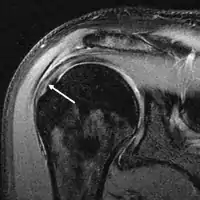

MRI

Magnetic resonance imaging (MRI) and ultrasound[46] are comparable in efficacy and helpful in diagnosis, although both have a false positive rate of 15–20%.[47] MRI can reliably detect most full-thickness tears, although very small pinpoint tears may be missed. In such situations, an MRI combined with an injection of contrast material, an MR-arthrogram, may help to confirm the diagnosis. It should be realized that a normal MRI cannot fully rule out a small tear (a false negative) while partial-thickness tears are not as reliably detected.[48] While MRI is sensitive in identifying tendon degeneration (tendinopathy), it may not reliably distinguish between a degenerative tendon and a partially torn tendon. Again, magnetic resonance arthrography can improve the differentiation.[48] An overall sensitivity of 91% (9% false negative rate) has been reported, indicating that magnetic resonance arthrography is reliable in the detection of partial-thickness rotator cuff tears.[48] However, its routine use is not advised, since it involves entering the joint with a needle, with the potential risk of infection. Consequently, the test is reserved for cases in which the diagnosis remains unclear.

Ultrasound

Musculoskeletal ultrasound has been advocated by experienced practitioners, avoiding the radiation of X-ray and the expense of MRI while demonstrating comparable accuracy to MRI for identifying and measuring the size of full-thickness and partial-thickness rotator cuff tears.[49] This modality can also reveal the presence of other conditions that may mimic rotator cuff tear at clinical examination, including tendinosis, calcific tendinitis, subacromial subdeltoid bursitis, greater tuberosity fracture, and adhesive capsulitis.[50] However, MRI provides more information about adjacent structures in the shoulder, such as the capsule, glenoid labrum muscles, and bone, and these factors should be considered in each case when selecting the appropriate study.